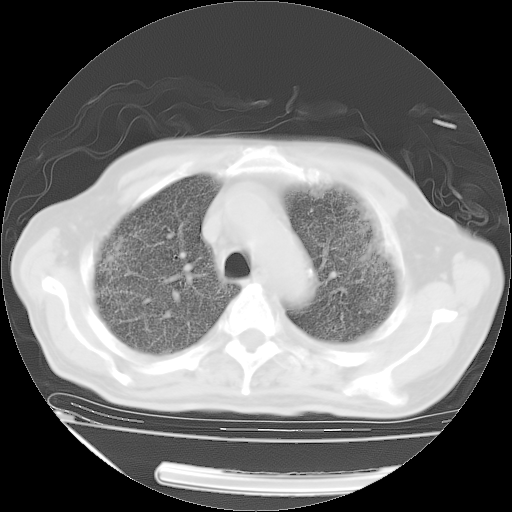

经过24天治疗,岳父的病情基本稳定。生活基本可以自理,可以下床活动。呼吸困难早已消失。体温基本正常。

只是甲强龙用80mg时血小板升到正常,改为60mg后又降到63×10*9/L。

主要治疗甲强龙80mg×14天,60mg×10天;同时抗结核(异烟肼+利福平+乙胺丁醇)。环磷酰胺0.1 tid 10天。

特别感谢胡教授、高管、桃子版主给出关键的治疗建议。桃版把所有肺部影像和全部临床资料请所在医院呼吸科、感染病科、结核科、临床免疫科专家会诊。临床免疫科专家制定了完整的治疗方案。